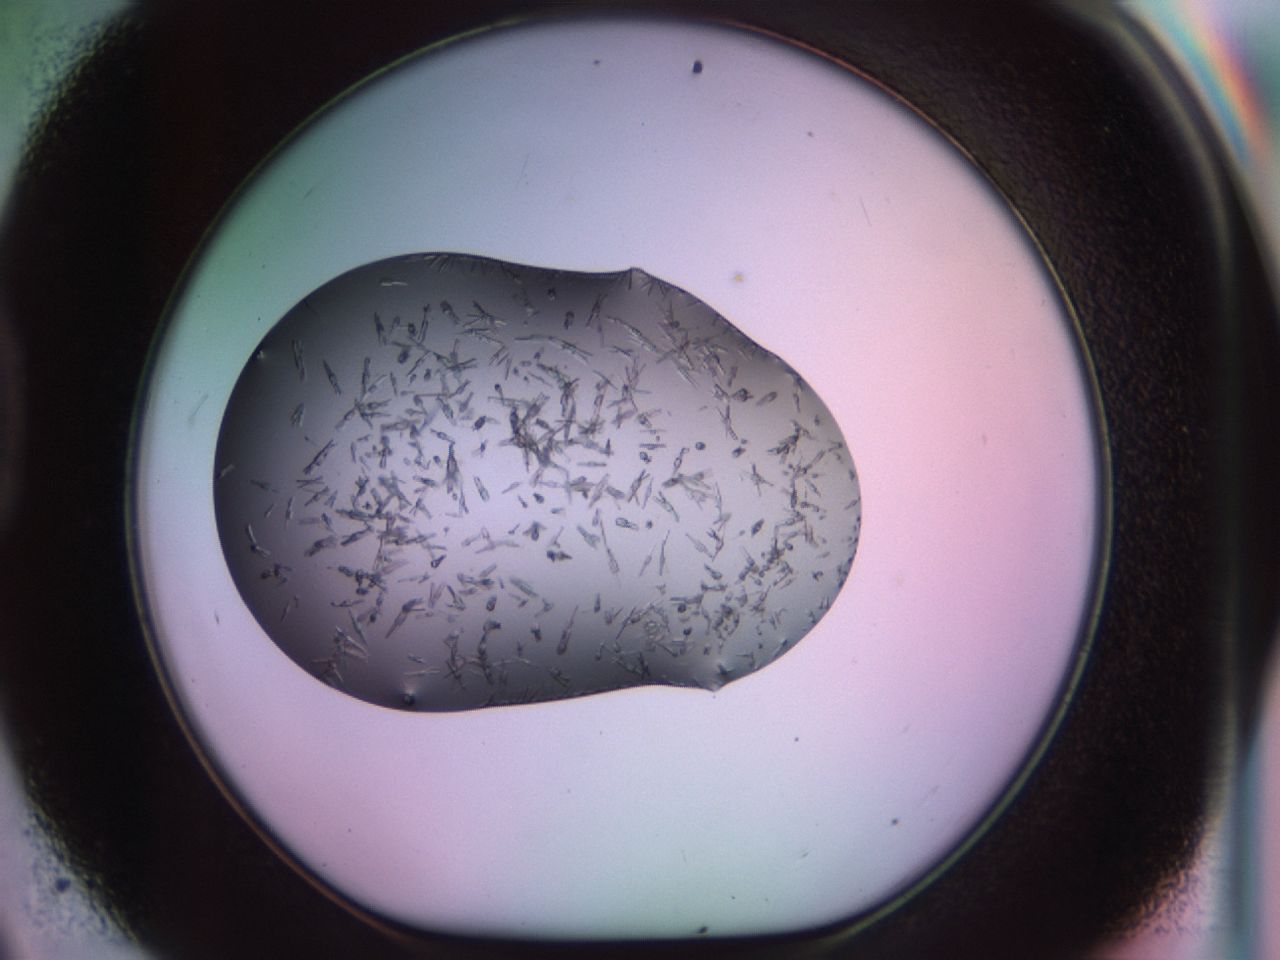

Crystals

Organization

GSK

02g1_D9_ImagerDefaults_8.jpg